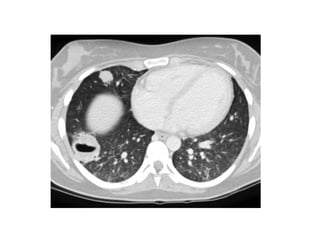

Bat wing edema in a 71-year-old woman with fluid overload and cardiac

failure, chest radiograph (a) and high-resolution CT

scan (b) demonstrate bat wing alveolar edema with a central

distribution and sparing of the lung cortex, the infiltrates resolved

within 32 hours